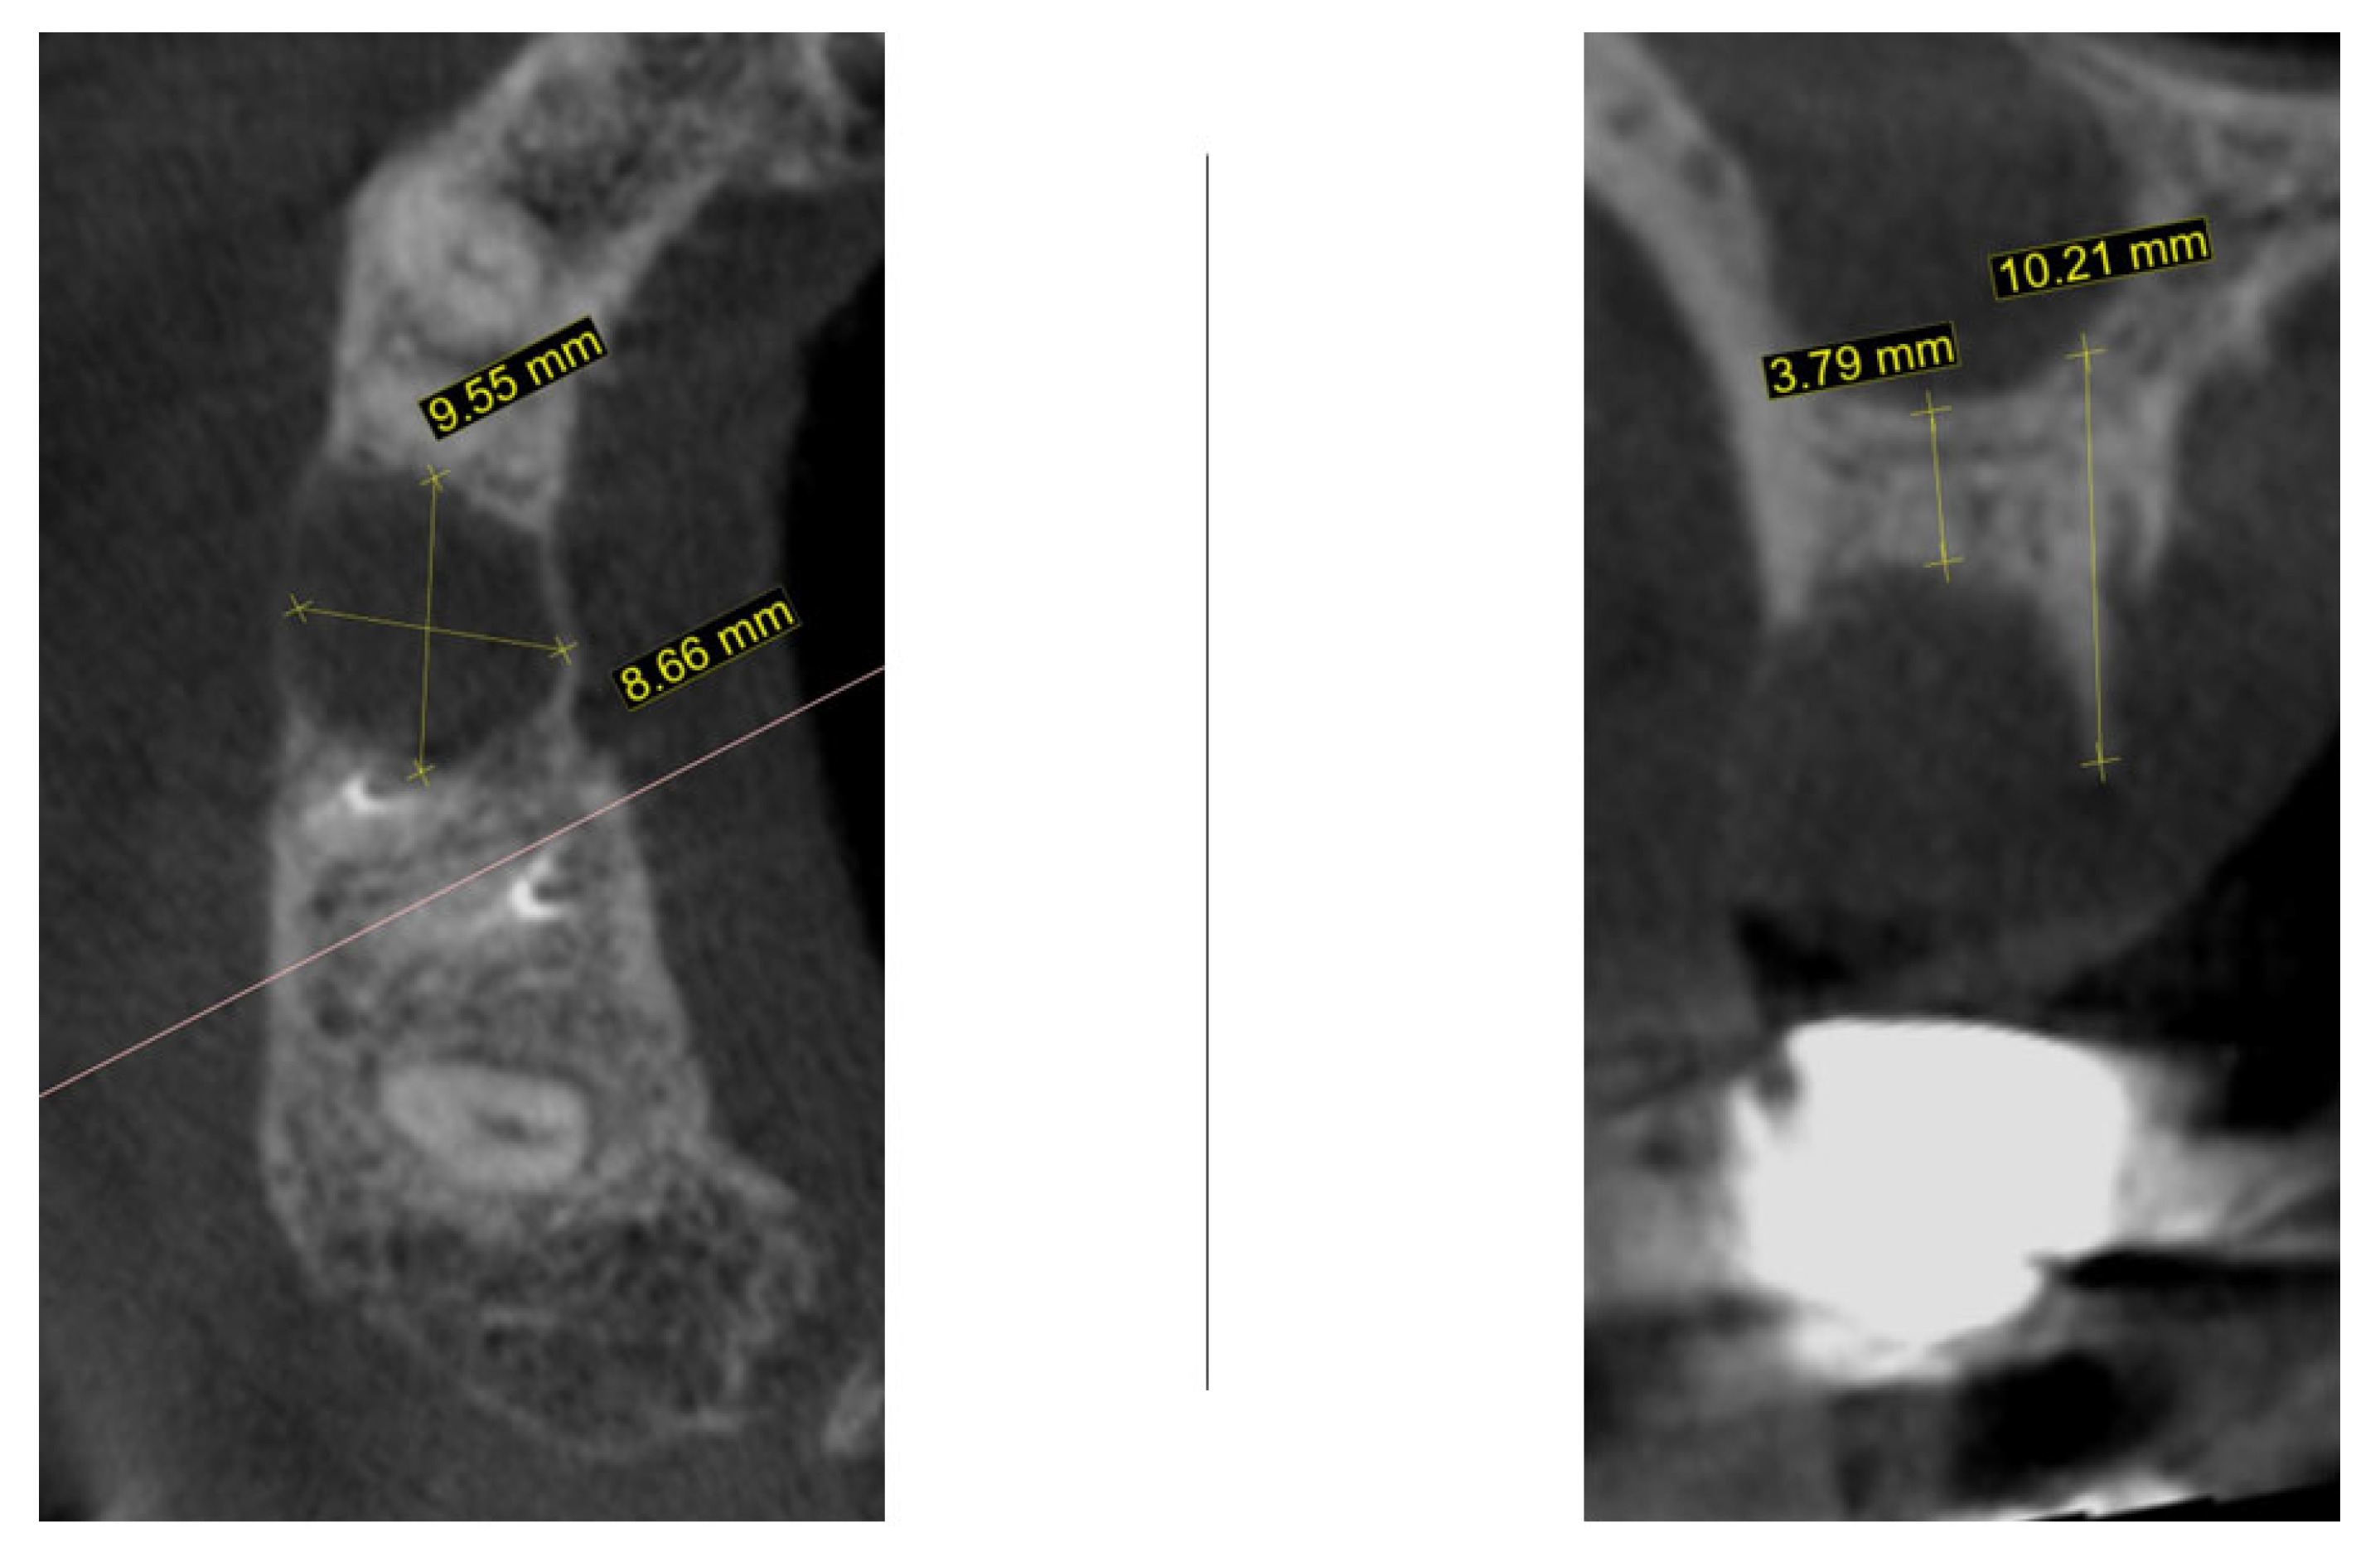

2. Materials and Methods—Clinical Case